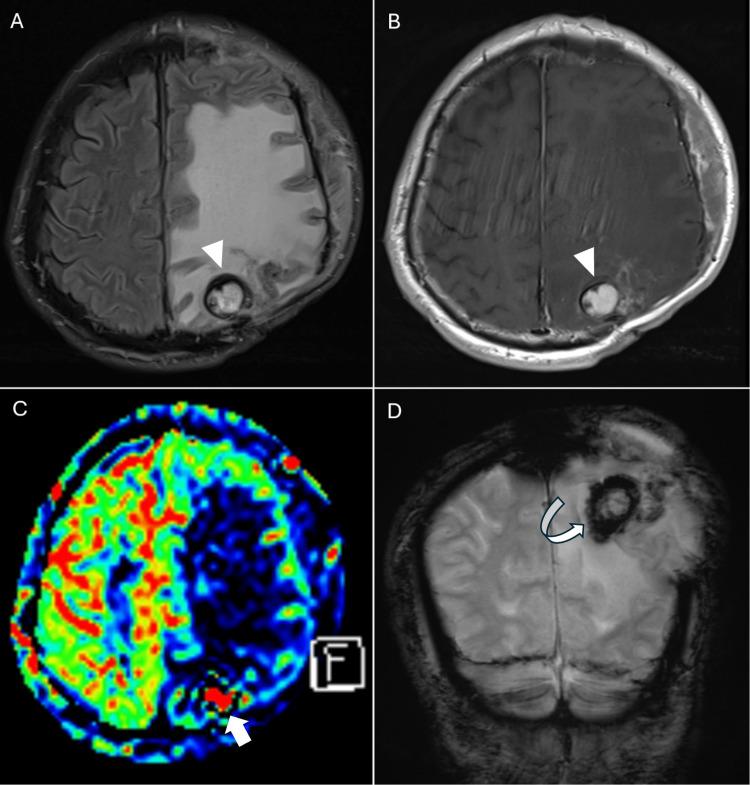

Chronic encapsulated expanding hematoma (CEEH) is a rare, delayed complication of stereotactic radiosurgery (SRS) for brain arteriovenous malformations (AVMs), often masquerading as radiation necrosis or tumor recurrence. We report the case of a 61-year-old man who developed progressive right hemiparesis and extensive steroid-resistant vasogenic edema 15 years after embolization and multisession SRS for a ruptured left parietal AVM, which had been previously confirmed as completely obliterated. Initial imaging showed a small enhancing lesion with surrounding edema, suspected to be radiation necrosis. Over the next two years, the lesion expanded with persistent edema despite corticosteroids and decompressive craniectomy. Follow-up MRI revealed classic hemorrhagic features, including a peripheral hypointense rim on T2*-GRE and SWI sequences, raising suspicion for CEEH. Surgical resection confirmed the diagnosis histopathologically and was followed by rapid clinical and radiological improvement. This case underscores the importance of considering CEEH in patients presenting with delayed symptoms and steroid-resistant edema after SRS, even when the lesion appears small. Early surgical recognition and intervention can be both diagnostic and therapeutic, preventing further morbidity.

慢性包裹性扩张性血肿(CEEH)是脑动静脉畸形(AVM)立体定向放射外科治疗(SRS)罕见的延迟并发症,常表现为放射性坏死或肿瘤复发。我们报告一例61岁男性病例,该患者在因左侧顶叶破裂性AVM行栓塞及多疗程SRS治疗15年后,出现进行性右侧偏瘫和广泛的类固醇抵抗性血管源性水肿,此前已证实该AVM完全闭塞。初始影像学检查显示一个小的强化病灶伴周围水肿,怀疑为放射性坏死。在接下来的两年里,尽管使用了皮质类固醇和去骨瓣减压术,病灶仍持续水肿并扩大。随访MRI显示出典型的出血特征,包括T2 * -GRE和SWI序列上的外周低信号环,这增加了对CEEH的怀疑。手术切除经组织病理学证实了诊断,随后临床和影像学迅速改善。该病例强调了在SRS后出现延迟症状和类固醇抵抗性水肿的患者中考虑CEEH的重要性,即使病灶看起来较小。早期手术识别和干预兼具诊断和治疗作用,可预防进一步的发病。